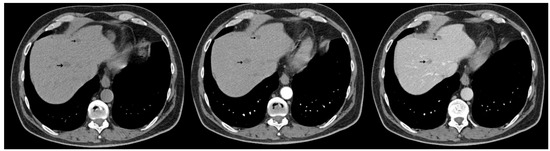

The thoracic contrast-enhanced CT scan provided a para-aortic mediastinal tumor mass with extension into the aortopulmonary window, raising further questions about the nature and origin of the hepatic and cecal lesions. The mediastinal mass was solid, heterogeneous, irregular, lobulated, and exobronchial, measuring 50× 30 × 45 mm. Additionally, lymphadenopathies were identified in the right inferior paratracheal, subcarinal, and paraesophageal regions, as well as adjacent to the left inferior pulmonary vein and the left interlobar area (Figure 5).

Figure 5.

Contrast-enhanced thoracic CT (axial, arterial phase; mediastinal window) demonstrates a lobulated mediastinal mass with heterogeneous enhancement, abutting the right pulmonary artery, measuring approximately 49 × 29 mm in the aortopulmonary window.